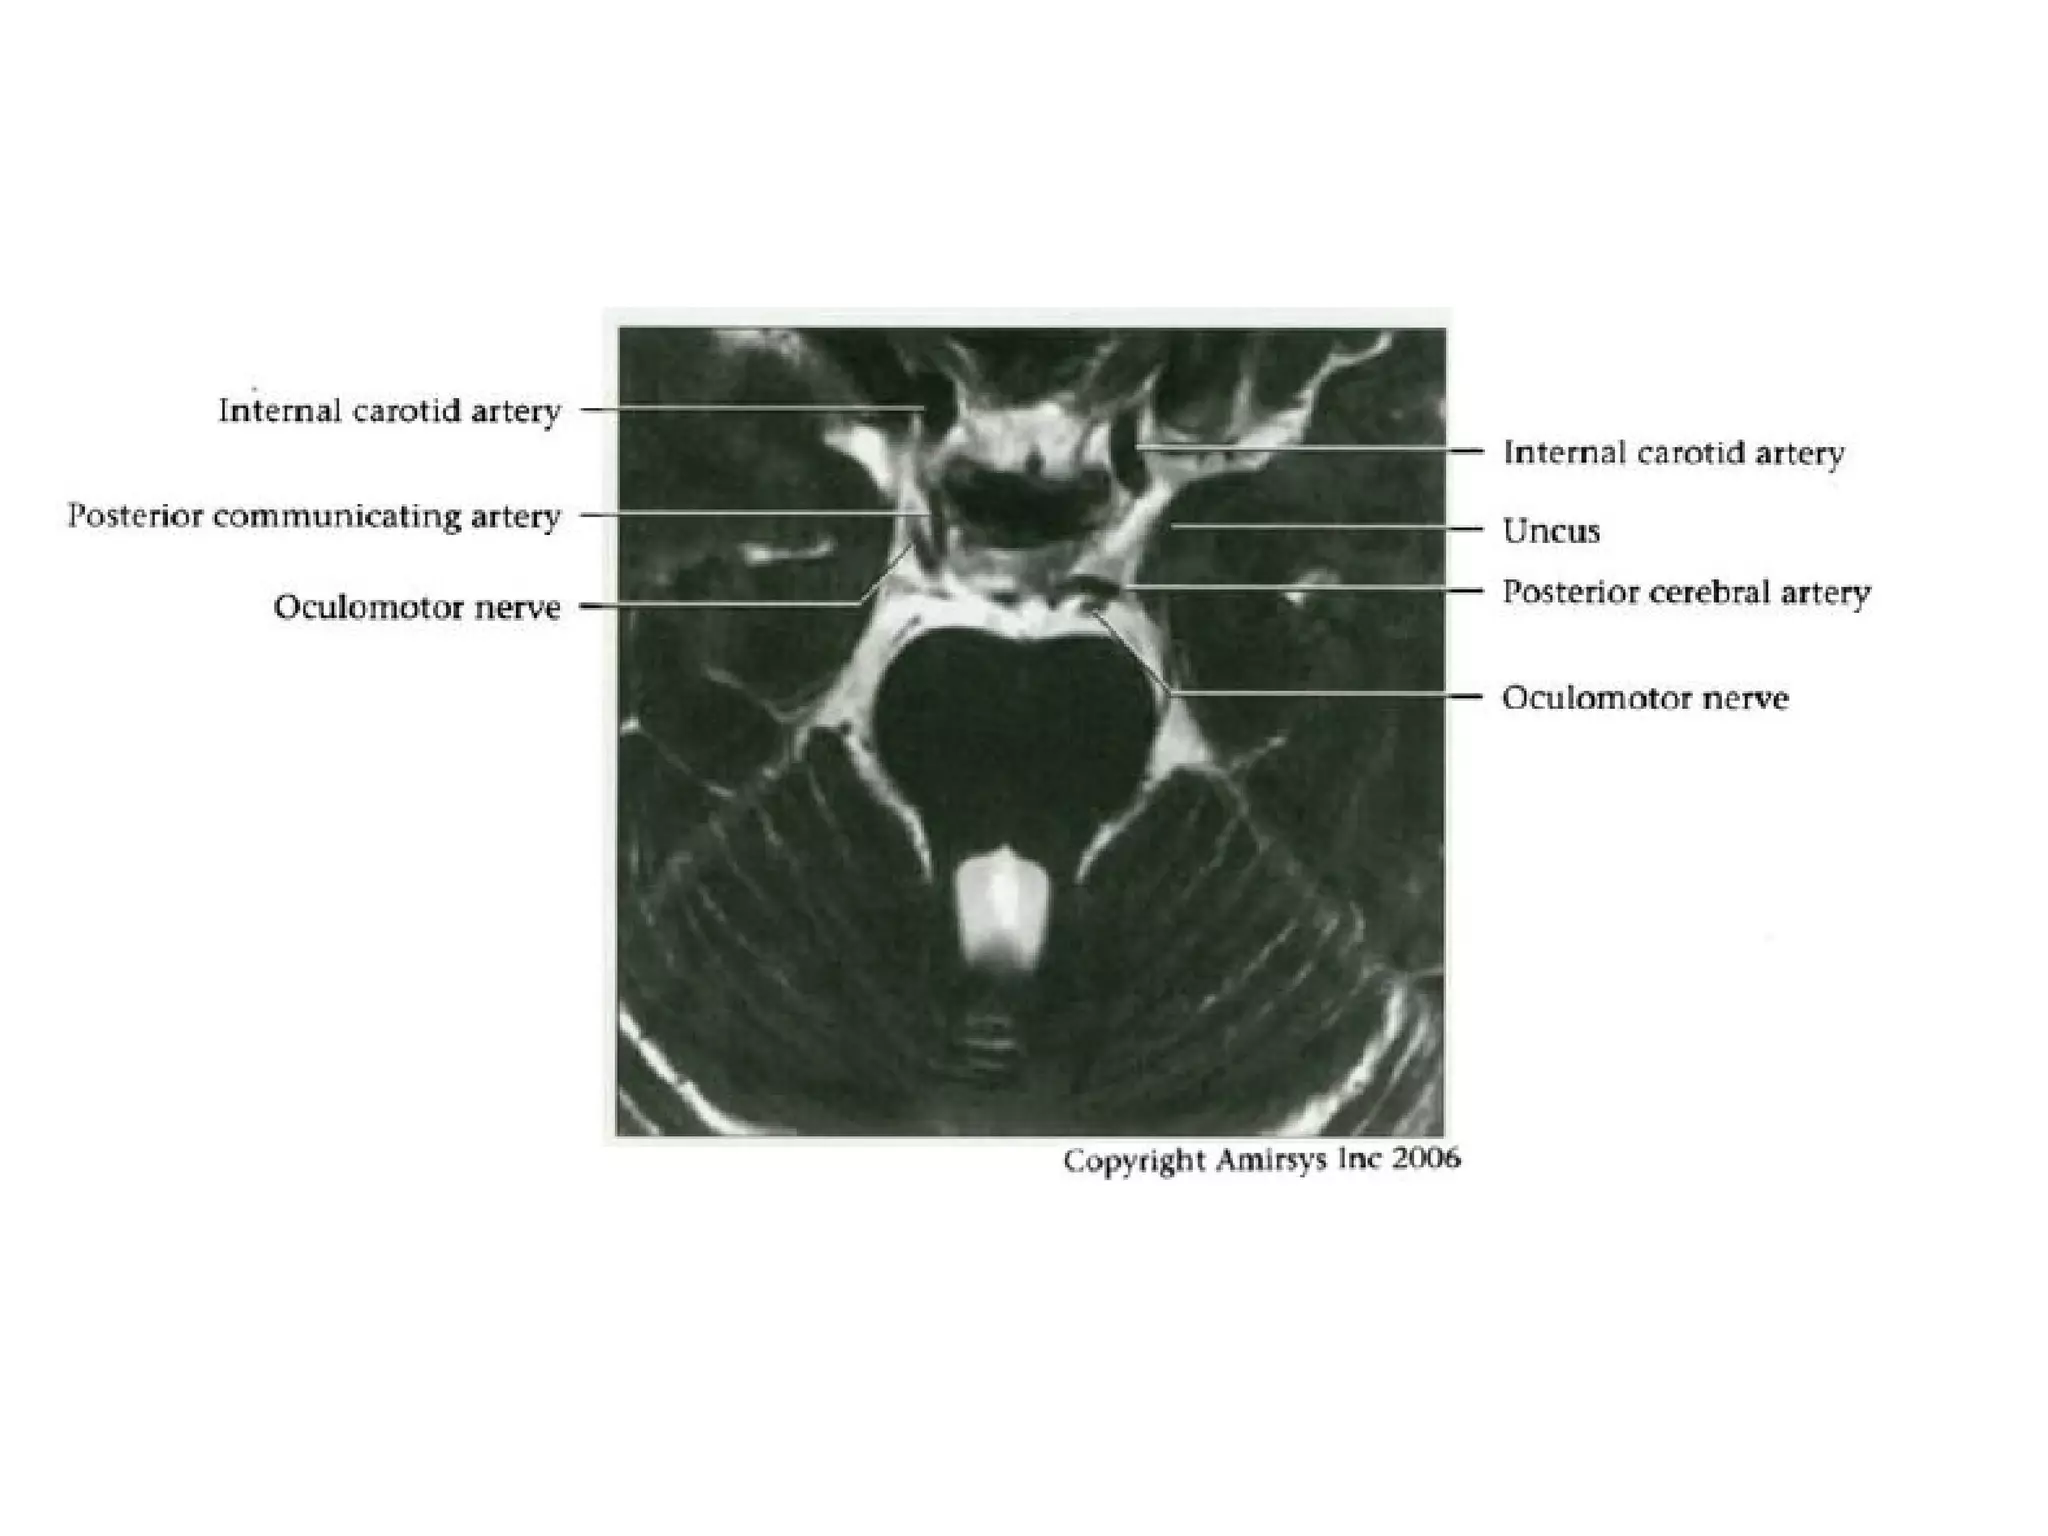

Cranial Nerve III:

The Oculomotor Nerve

• The oculomotor nerve originates from nuclei deep to the

superior colliculus, ventral to the cerebral aqueduct, and

inferior to the pineal gland.

• The nerve then travels across the midbrain from

posterior to anterior.

• The oculomotor nerve root emerges into the

interpeduncular cistern, and this root entry zone in the

cistern is a good way to identify the oculomotor nerve on

axial SSFP MR images.

• In the prepontine cistern, the nerve travels between the

superior cerebellar and posterior cerebral arteries, which

makes it easy to identify on coronal SSFP images.

• The cavernous segment of the oculomotor nerve

runs along the lateral wall of the cavernous sinus

and is the most superior of the nerves in this

sinus.

• The oculomotor nerve then enters the orbit

through the superior orbital fissure, before

splitting into superior and inferior divisions lateral

Oculomotor nerve.

Axial oblique 0.8-mm-thick SSFP MR image shows the nerve (small arrows) where it emerges

from the interpeduncular cistern (large arrow), which lies medial to the cerebellar peduncle (p).

Coronal 0.8-mm-thick SSFP MR image shows the oculomotor nerve (white arrow) in cross section

between the posterior cerebral artery (white arrowhead) and the superior cerebellar artery (black

arrowhead), which are distal branches of the basilar artery (black arrow).